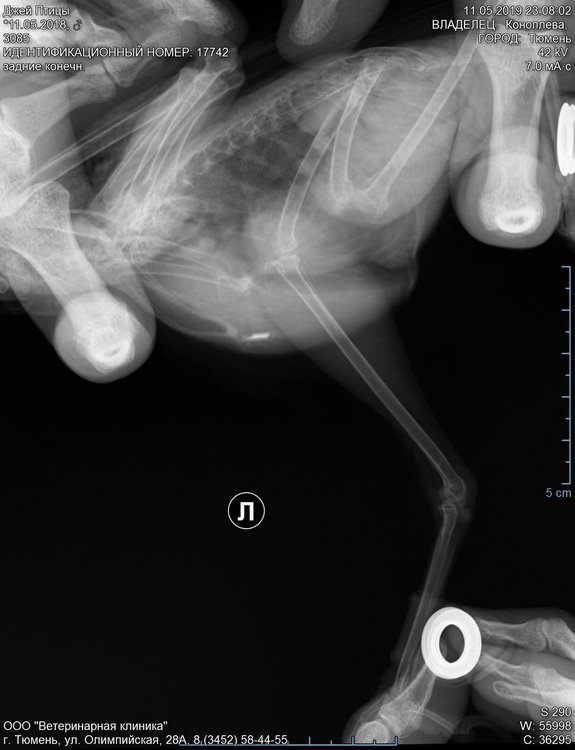

ситуация такая: около 3-3,5 недель назад был поставлен чип (100 раз уже пожалела). начиная со следующего дня, птица сначала начала поджимать лапу, со стороны введения этого самого чипа, а затем и вовсе перестала на нее наступать. был сделан рентген(прилагаю) и поставлен диагноз: трещина в кости. прописали Онсиор внутримышечно 3 дня, кальциеборглюконат 10 дней совместно с витаминами аде(1р/2 дня) и Травматином, затем Calcium 8в1 и покой в виде ограниченного пространства. птица начала идти на поправку, через 2 недели уже стала осторожно наступать на лапу, пытаться скакать, активно разговаривать и клеваться. дня 4 назад снова стала аккуратнее с лапой, больше поджимать ее. внимание особо не обратила, поскольку не ново, а затем сама слегла с жуткой температурой. вставала только дать еду с суточной дозой кальция. что стало моей фатальной ошибкой. через дня 1,5-2 взяла птицу на руки и обнаружила, что лапа сильно распухла. пришлось экстренно срезать манжет, что, скорее всего, и привело к активному кровотечению. кровь вроде удалось остановить марганцовкой. в единственной клинике, где нас согласились принять посреди ночи с таким зверем, смогли только еще раз обработать лапку, окончательно остановив кровь, перебинтовать не туго и дать глюкозы. больше ничем помочь не могли. на следующий день наш врач не принимал, а поездка в другую клинику закончилась снятием повязки и "это все манжеты натерли, снимайте и будет вам счастье, ничего больше не нужно". после снятия повязки помет примерно час имел коричневый цвет, затем нормализовался. на следующий день наш врач направила на повторный ренген в другую клинику(тоже прилагаю). рентгенолог поставил предварительный диагноз: остеомиелит. подробно показал разницу с прошлым снимком, изменение в структуре кости. и вот, сегодня на приеме лечащий врач дала свой диагноз:перелом, продолжаем кормить кальцием. говорит, птица хрупкая, ломается вся. как и почему остается загадкой. если трещина в кости весьма могла образоваться в результате фиксации на приеме, то перелом не увидел ни рентгенолог, ни, честно говоря, я сама, хотя очень старалась. безумно переживаю, что это может оказаться остеомиелит или еще какое серьезное заболевание, требующее незамедлительного лечения, и ждать пока они не станут запущенными и очевидными времени нет...

первый ренген.jpg

второй ренген.jpg

второй ренген2.jpg